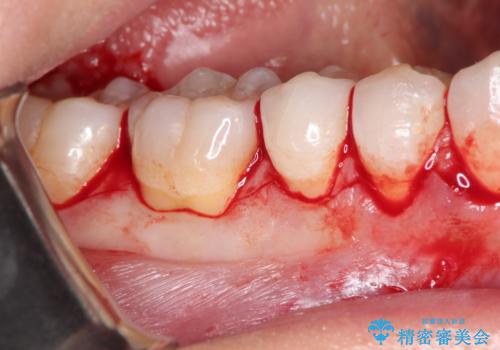

- 昔に受けた矯正治療がきっかけで歯肉が下がってしまった事を主訴として来院された患者様です。

結合組織移植術を行う方法を提案しましたが、傷口が口蓋にもできるのが嫌だとのことで、代替案としてバイオマテリアルを併用した根面被覆術を計画致しました。

治療対象部位は右下4,5,6番の3本です。